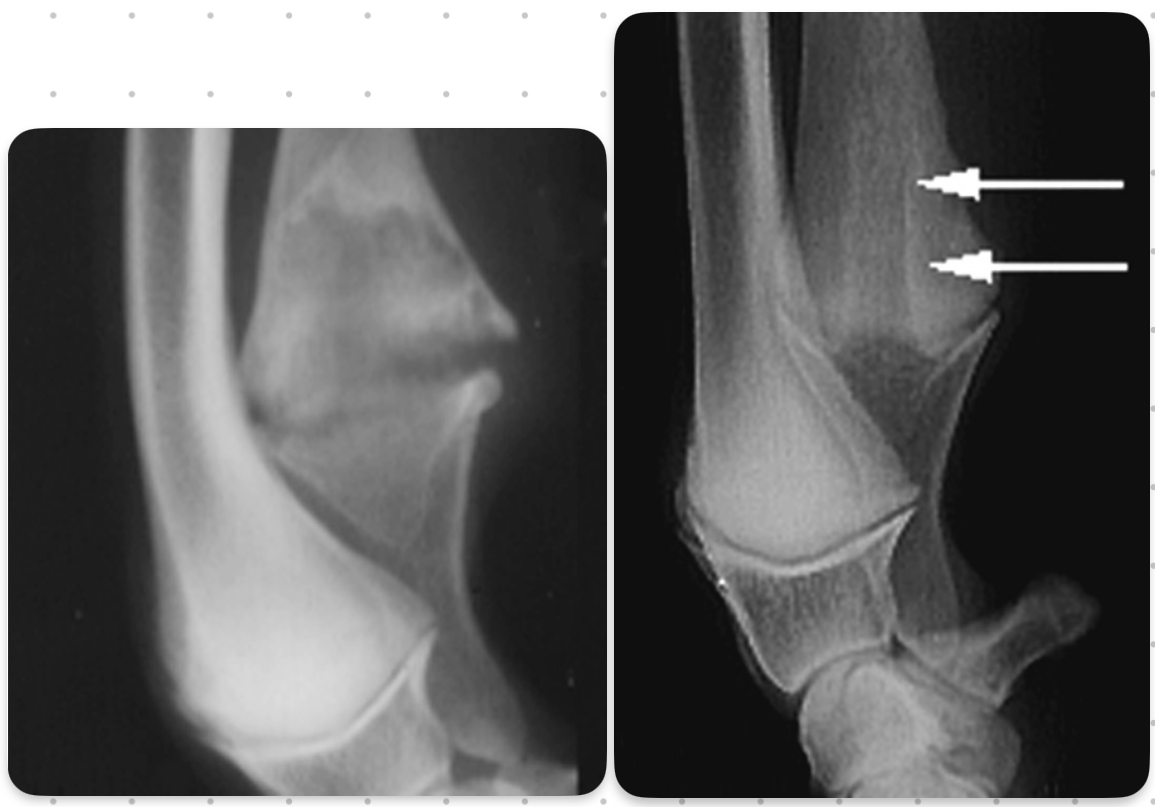

UME signalment

Labradors, GSD, english setters

6 - 12 mo age

UME

look for thing off to the side of medial epicondyle